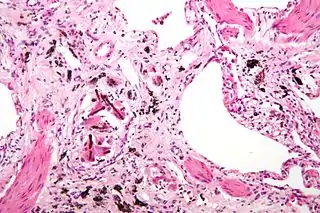

![]() Micrografía de asbestosis que muestra los cuerpos ferruginosos característicos y marcada fibrosis intersticial (o cicatrización). Tinción hematoxilina-eosina. | ||

El amianto es una sustancia inorgánica que al acumularse de forma progresiva y continuada produce destrucción y posteriormente cicatrices pulmonares crónicas debido a la incapacidad de las células de defensa pulmonar (macrófagos) de digerir y eliminar adecuadamente este material inorgánico. Estas cicatrices impiden el normal funcionamiento pulmonar (disminución de la expansión pulmonar por fibrosis, intercambio gaseoso), lo que explica los síntomas de la enfermedad.

Se produce así una neumoconiosis caracterizada por una fibrosis pulmonar (enfermedad pulmonar intersticial). Está asociada a mesotelioma y carcinoma broncogénico.